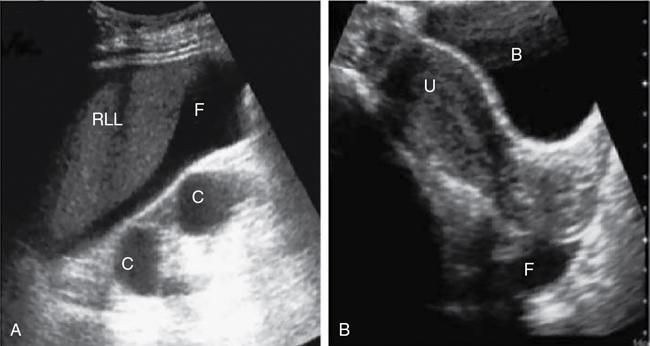

Amandeep Singh Trauma is one of the leading causes of morbidity and mortality. Blunt abdominal trauma accounts for 5% of trauma-related mortality and also contributes to 15% mortality polytrauma related mortality. More than 90% of the injuries are minor injuries and can be conservatively managed. In 10% of patients, serious injuries occur, like vascular bleeding, grade 4 or higher injuries of visceral organs, pseudoaneurysm formation, contrast or pelvicalyceal system (PCS) injury, all these require active intervention. Acute cause of death is mainly due to vascular bleed. Most common visceral organ affected in abdominal trauma is spleen followed by liver. The proper evaluation must be done of patient suffering from abdominal trauma. Abdominal trauma could be either penetrating or blunt. Blunt trauma occurs in patients of motor vehicle accidents, assault, falls and industrial accidents. Gunshot injuries and stab wounds lead to penetrating abdominal trauma. Many latest advances have been made in field of radiological imaging and imaging-guided interventional therapies, which enables nonsurgical management of haemodynamically stable patients with abdominal trauma. Contrast-enhanced computed tomography (CECT) is the investigation of choice for solid organ injures evaluation. Multidetector computed tomography (MDCT) can also help in detection of both vascular and visceral injuries following blunt abdominal trauma, for quicker examination. Thus, fast and accurate diagnosis plays a critical role in the management of patient. For appropriate care of patient imaging guideline has been recommended that includes (Fig. 7.14.1): So in haemodynamically unstable patients with blunt abdominal trauma we require: The chest X-ray erect is the earliest and most sensitive investigation for evaluation of pneumoperitoneum. With optimal radiographic technique and proper upright positioning of the patient for at least 10–15 minutes are required to detect even a small amount of air. It is possible to demonstrate up to 1.0 cc of free air on upright chest radiograph. However, plain radiographs of the abdomen are not the appropriate investigation of choice for the detection of haemoperitoneum. More than 800 cc volume of intraperitoneal blood volume is usually necessary for the demonstration of classic plain radiographic signs, for example ‘dog ear’ or ‘bladder ear’ sign when there is accumulation of intraperitoneal blood in the pouch of Douglas. Paracolic gutters are the most dependent intraperitoneal areas are where the collection of blood occurs which further displacing the right or left colon medially. The FAST is a technique for assessment of haemoperitoneum and hemopericardium (Figs. 7.14.1 and 7.14.3). It has sensitivity and specificity of more than 85% and 98%, respectively. Recently extended FAST (eFAST) protocol has come into the trauma algorithms. The eFAST examines each hemithorax for the presence of hemothorax. The FAST exam assesses the pericardial cavity and peritoneal spaces for fluid. The right upper quadrant (RUQ) evaluates the hepatorenal recess/Morrison’s pouch, the right paracolic gutter, the subdiaphragmatic area, and the caudal end of the left lobe of liver (Fig. 7.14.4a). Overall sensitivity for the detection of free fluid in the RUQ view is approximately 66%. Next is the subxiphoid (or subcostal) views to evaluate the pericardial space for any free fluid. Ultrasound detects as little as 20 cc of pericardial fluid and studies have shown excellent sensitivities and specificities approaching 100%. The subcostal view is to be required for differentiating pleural and pericardial. Left upper quadrant (LUQ) view is helpful to inspect the splenorenal recess, the subphrenic space, the left paracolic gutter and the left lower hemithorax during performing (eFAST). Similar views of the right hemithorax are obtained when scanning the RUQ. For each hemithorax view, probe has to be slide cranially above the diaphragm. The presence of the hyperechoic vertebral bodies, or ‘spine sign’, helps in identifying the fluid in the pleural cavities. US has sensitivity and specificity of 92%–100% in detection of hemothorax. Suprapubic view is beneficial in evaluating free fluid in the rectovesical pouch and cul-de-sac (rectouterine and vesicouterine) in males and females, respectively (Fig. 7.14.4b). There are no absolute contraindications to the eFAST. Curvilinear probe of frequency 2–5 MHz is used for the eFAST exam to reduce delays when switching between transducers. Likewise, the 5–12 MHz linear (or vascular) probe is ideal for assessing for pleural sliding. Although MRI does not play a role in the initial evaluation of blunt abdominal trauma. However, MRCP may be specifically useful in detecting biliary leaks. Angiographic embolization is needed when there is evidence of vascular injury (pseudoaneurysm, arteriovenous fistula) on CT scan and inactive contrast extravasation as an alternative to surgery. There is a great role of angiography in providing haemostasis in haemodynamically stable patients with high grade (IV and V) liver and spleen injuries. Computed tomography is now used as the principal imaging modality for diagnostic evaluation of abdominal trauma. It is useful in detecting both intraabdominal and retroperitoneal structure injuries and grading severity of specific parenchymal injury, along with evaluation of associated injuries of head and chest. Advantages of CT over DPL, includes detailed evaluation of injuries, associated haemorrhage and detection of any contrast extravasation. DPL has now almost become obsolete. Following a negative abdominal CT study using helical scanner, trauma patients can be discharged without a period of observation. Intravenous contrast bolus of 100–150 mL (350 mg of iodine per millilitre with total iodine load of 35–52.5 g) injected at a rate of 3–5 mL/s via 18–20 gauge cannula placed in a large peripheral vein is administered in all trauma patients. Single bolus injection method is widely used. A split bolus technique has also been proposed which has minimized the radiation exposure as a single acquisition is performed for evaluation of the abdomen. Oral contrast material for evaluating patients is no longer administered at most large trauma centres in the setting of blunt trauma. CT protocol includes portal venous phase images of the abdomen and pelvis, which are acquired at the interval of 65–80 seconds after the beginning of intravenous contrast material administration. Along with portal venous phase series, delayed phase (5–10 minutes after intravenous contrast material administration) images are necessary for patients within the amount of radiation delivered. Those with severe injury and those who have a displaced fracture of the pelvic ring, addition of an arterial phase (25–30 seconds after injection) of the abdomen and/or pelvis is required. Arterial phase helps in detection of vascular trauma that is not well appreciable on portal venous or delayed phases. With speed afforded by 64-detector scanners (and beyond), these CT angiograms can be comprehend protocols that use a single bolus of intravenous contrast material. CT cystography is done in patients suspected of bladder injury. It requires instillation of 300–400 mL of diluted water-soluble contrast material (40 mL of contrast in 360 mL of normal saline) into urinary bladder through a Foley catheter. In case of severe polytrauma, the CT cystography is done along with the delayed phase of the abdomen and pelvis which limits the radiation dose. However, it still requires full active distention of the bladder. Spleen is the most frequently injured organ following blunt abdominal trauma. Splenic injuries account for approximately 40% of all solid organ injuries occurring in abdominal trauma. Contributory factors include its potential for injury from fractured ribs, intraabdominal compression and its rich vascular supply. CECT abdomen is the modality of choice for imaging splenic injuries. Spleen shows heterogeneous enhancement on arterial phase and hence can simulate injury. So, the images should be obtained in portal venous phase. If there is dense contrast pooling seen within or around spleen, delayed CT images should be obtained to differentiate active bleeding from posttraumatic vascular injuries. Active bleeding retains the same density or even may increase in attenuation in delayed phase. Delayed phase may also be useful in differentiating a laceration from a splenic cleft. A cause of the potential inaccuracy of CT is the entity of delayed splenic rupture. Delayed splenic rupture can occur up to 48 hours after blunt trauma which should be differentiated from delayed presentation of splenic rupture due to a minor injury. On contrast-enhanced CT, splenic lacerations appear as linear low-attenuation defects within the splenic parenchyma. Shattered spleen may result due to combination of complex interconnecting lacerations. Intrasplenic haematomas appear as more diffuse hypo-attenuating regions. Splenic infarcts appear as triangular peripheral nonenhancing regions and must be distinguished from splenic haematomas. Subcapsular haematomas may occur alone or in combination with other injuries and result in low-attenuation collections that indent the splenic margin. The various CT manifestation of splenic trauma are: